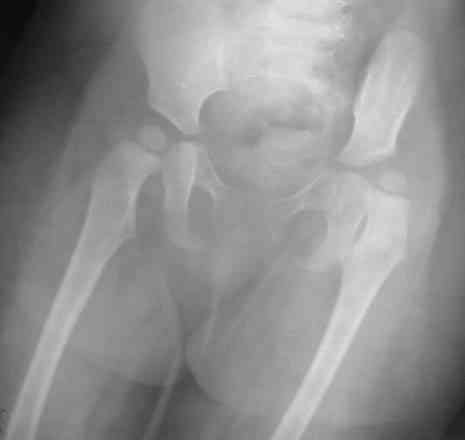

Уважаемые коллеги! Окажите, пожалуйста, консультативную помощь! Девочка, 1 г 9 м ДЗ: врожденная патология головного мозга, врожденная дисплазия, подвывих, приводящая контрактура левого тазобедренного сустава, микроцефалия, миоклонические припадки, грубая задержка психофизического развития, с-м Айкарди?

Жалобы родителей на укорочение левой ноги, невозможность ходить, сидеть. Впервые обратили внимание на укорочение левой нижней конечности 4 месяца назад. Осмотрена по месту жительства в ЦРБ, направлена в ДНИИТО. Ребенок от I беременности, I срочных родов, протекавших с анемией, осложненные преждевременным отхождением вод, вес при рождении 4100. В анамнезе - пупочная грыжа, респираторные заболевания, рахит, тетрапарез, судорожный синдром, сальмонельоз.

Особенности объективного осмотра в настоящее время: Умеренный тетрапарез. Признаки рахита (деформация костей черепа, четки). Дыхание пуэрильное. Тоны сердца ритмичные, шумов нет. Живот мягкий, безболезненный, печень +1,5 см. Склонность к запорам. Местный статус: резкое приведение левого бедра, относительное укорочение левой нижней конечности. Ограничение отведения в тазобедренных суставах, особенно слева. Гипертонус мышц левой нижней конечности. Ограничение сгибания в левом коленном суставе.

Объем движений (левый ТБС): сгибание-разгибание (фиксированное) 65-165; разведение - D 45, S 65. Положение сустава по отношению к линии Розера-Нелатона - D 0,5 см, S 1,5 см. Хронаксиметрия - возбудимость нервных стволов нижних конечностей в норме, двигательная реакция мышц типичная.